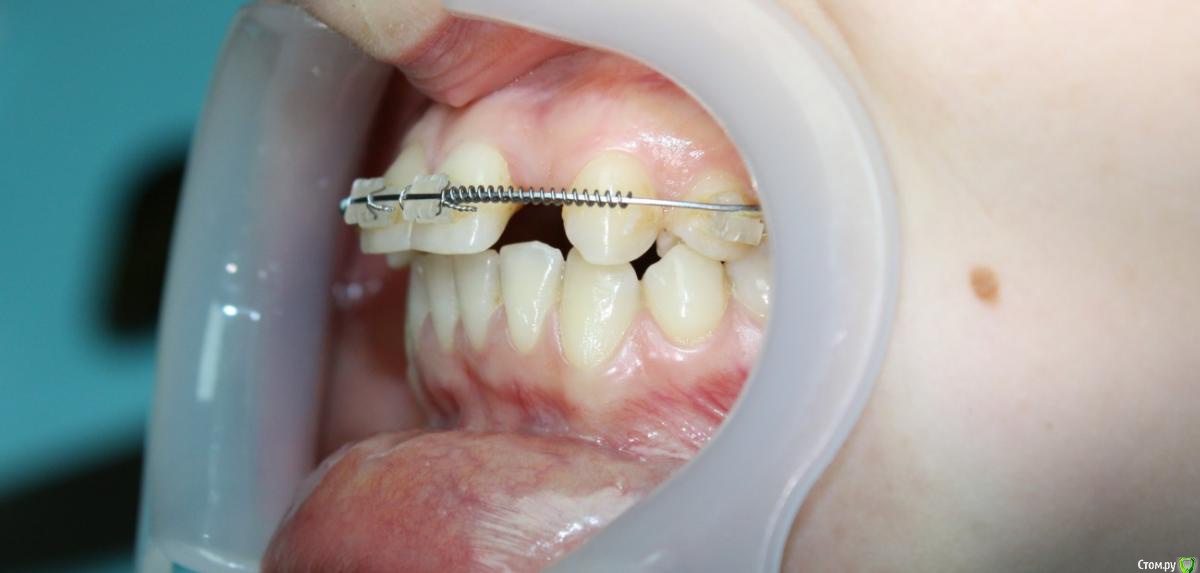

Здравствуйте коллеги! На консультацию обратилась пациентка, сейчас находится на ортодонтическом лечении. Предистория: три года назад обратилась к стоматологам с жалобой на неудовлетворительную эстетику фронтального отдела, вследствие врожденного отсутствия латеральных резцов. Ей было предложено ортодонтически создать место для боковых резцов, затем провести имплантацию и протезирование на имплантатах 12, 22.

Затем, с ее слов, идет длительный этап ортодонтии, почти 3 года, вследствие которого получили немного места для двоек, которого не достаточно для иплантации, так же центральные резцы ушли вперед, образовалась саггитальная щель.

Ортодонт предлагает удалять восьмерки, ставить брекеты Дэймон на вч и нч, мини винты в ретро молярную область  и продолжать ортодонтическое лечение, создавать место для двоек. Пациентка пока пошла делать новое КТ,

Фото сегодня:post-461-0-94195200-1456407270_thumb.jpgpost-461-0-97652100-1456407271_thumb.jpgpost-461-0-40898500-1456407273_thumb.jpgpost-461-0-68973300-1456407274_thumb.jpgpost-461-0-88108800-1456407275_thumb.jpgpost-461-0-99061300-1456407276_thumb.jpgpost-461-0-92547500-1456407277_thumb.jpgpost-461-0-02811200-1456407279_thumb.jpgpost-461-0-05035300-1456407280_thumb.jpgpost-461-0-27197600-1456407281_thumb.jpg